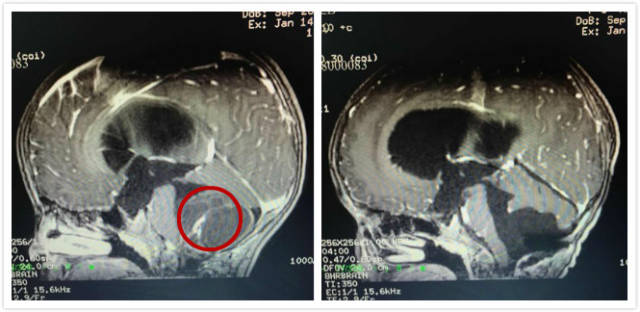

42岁的林女士(化名)因头痛眩晕、四肢麻木,检查发现脑干及颈髓腹侧胆脂瘤。日前,南方医科大学中西医结合医院神经外科团队为其手术,顺利切除了颅内肿瘤。术后,林女士恢复良好,语言、肢体功..

疫情期间,42岁的潮汕商人林女士因周身乏力、头疼眩晕且心跳加速,伴有四肢发抖、麻木、手脚出汗在当地医院检查发现脑干及颈髓腹侧占位性病变,转至南方医科大学中西医结合医院求医。